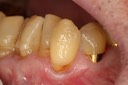

Ted Kanamori #24 pre-op

Ted Kanamori #24 prep